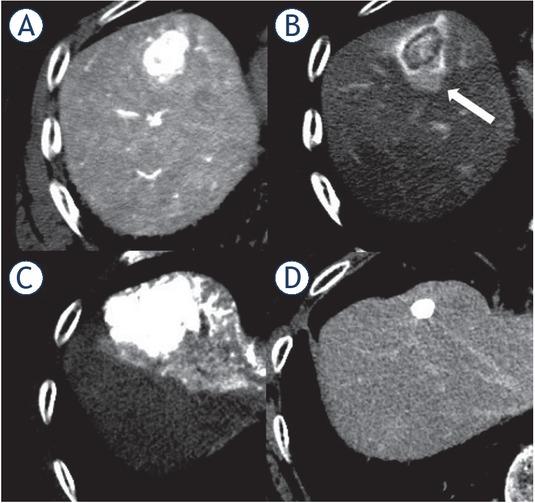

Figure 2